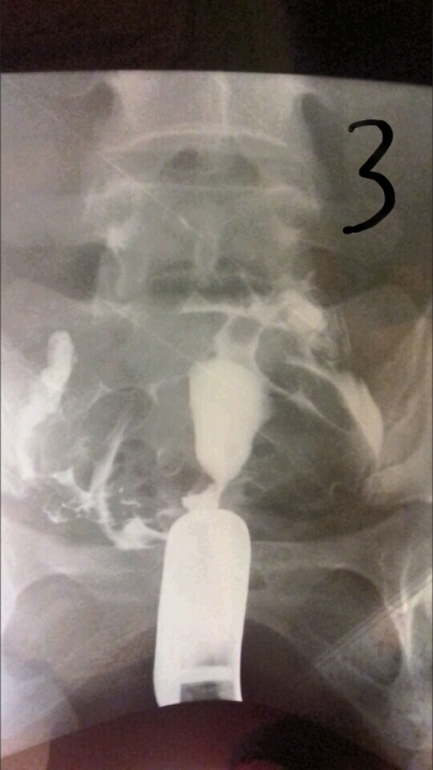

Лапароскопия, гистероскопияДобрый день девочки. Не знаю раздел куда написать, но думаю сюда. Сделала я гсг проверку труб рентгеном. Жидкость прошла, но не сразу, минут так 5 думаю лежала, хотя может меньше. Показало спайки в брюшной полости и вроде как в ампулярных отделах, так как они были расширены при поступлении контраста. И также сказали, что спайки скорее всего из-за эндометртоза. Кто сталкивался с такими проблемами, может подскажите, что по этому и по снимкам.

Полностью согласна. Все эти процедуры ведут только к лапаре. И гистероскопия также проводится в диагностических целях. Ну пробьют они раствором трубы, но это я думаю особой пользы не приносит. На снимках видно, что жидкость изливается в брюшную полость, значит проходимость есть, но если частичная, это уже не то. Так что не тчните, ларара, пару месяцев если еб нет и на Эко.